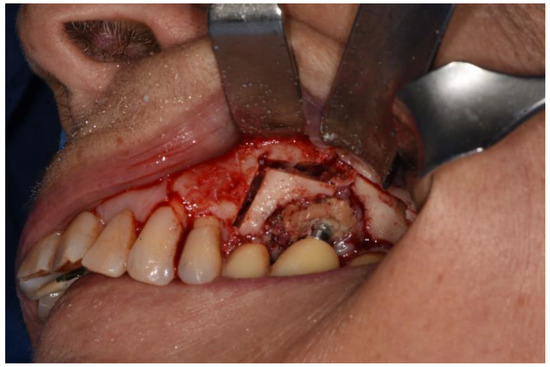

Figure 3. Full thickness flap elevation.

Therefore, a full-thickness vestibular flap was set up with medial and distal release incisions to oroantral communication (already present or induced as a result of extraction of dental element, bone implant or excision of lesion due to sinus pathology) and bone defects known. Ostectomy and osteoplasty were performed, if necessary.